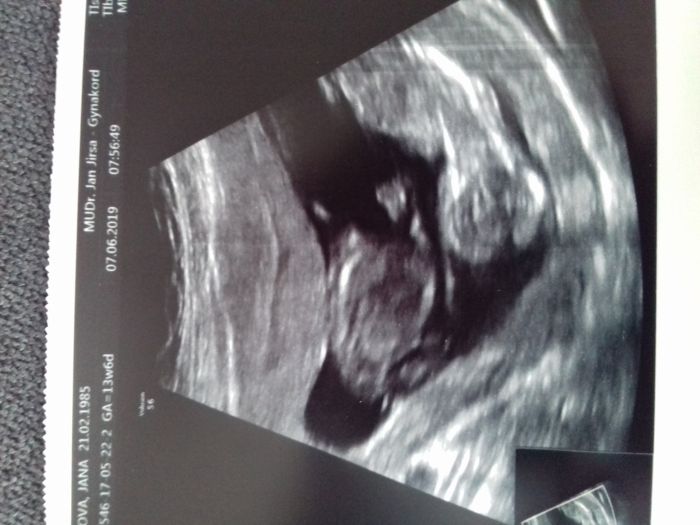

Tak mám pocit screeningu a dopadl moc dobře. Všechno je v pořádku. Termín porodu podle ultrazvuku mam 13.12.a na 80 %to budou holčičky, už sme premyslely o jménech a bude to Verunka a Terezka

. Na další kontrolu jedu do Olomouce 1.7. Sem strašné ráda, že je všechno v pořádku.